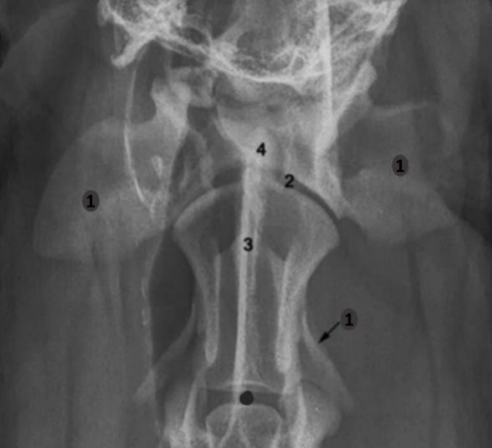

Analise a imagem radiográfica a seguir.

Pela análise da imagem, quais são as partes ósseas identificadas pelos números 1, 2, 3 e 4, respectivamente?